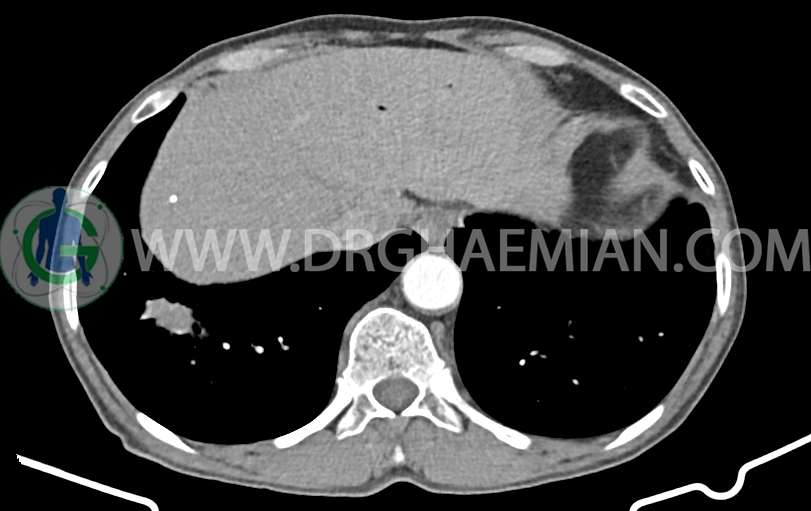

در سی تی اسکن اسپیرال ریه، مدیاستن و شکم و لگن با کنتراست خوراکی و وریدی (مولتی دیدکتور 16 با مقاطع ظریف و بازسازی های ساژیتال و کرونال) و مقایسه با سی تی اسکن 1401/06/06:

توده با حدود اسپیکوله به ابعاد mm 51x33x24 حاوی چند کانون کلسیفیه کوچک در قاعده ریه راست مجاور دیافراگم مشهود است که مطرح کننده ضایعه نئوپلازیک مثل توده اولیه و متاستاز می باشد. (نیازمند بررسی بافتی – یافته جدید نسبت به سی تی اسکن 1401/06/06 (

کانون کلسیفیه کوچک فاقد اهمیت بالینی در لوب راست کبد رویت شد